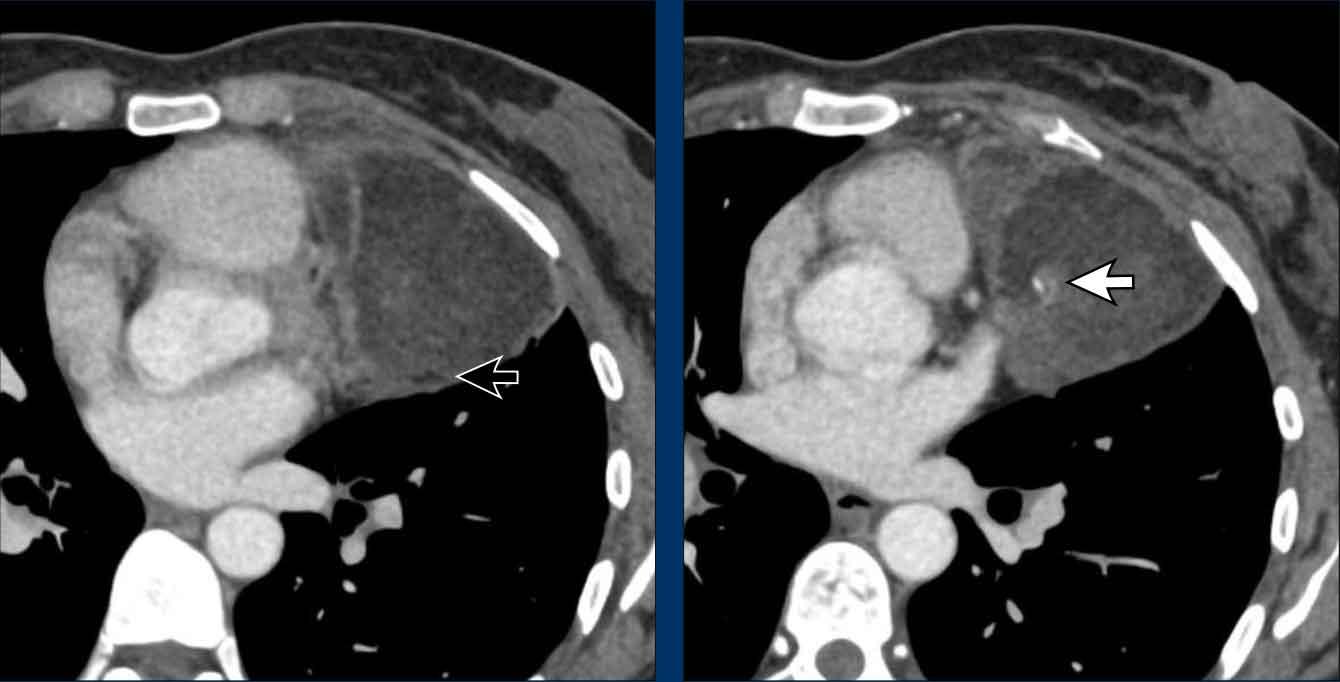

Các hình ảnh này của một phụ nữ 34 tuổi có triệu chứng khó thở.

Hãy phân tích các hình ảnh.

Nhận định của bạn là gì?

Hình ảnh

Có một khối nang ở khoang trung thất trước mạch máu.

Thành nang dày và có ngấm thuốc cản quang.

Do vẫn chưa rõ bản chất tổn thương, PET scan đã được thực hiện.

Tiếp tục xem các hình ảnh PET…

Dựa trên kết quả PET, chẩn đoán nào là có khả năng nhất?

Đây là u tuyến ức dạng nang, nang biến chứng, u thần kinh nội tiết hay u lympho?

PET cho thấy nhiều tổn thương, đây phải là các hạch bạch huyết bệnh lý.

Thảo luận

U tuyến ức hầu như không bao giờ đi kèm với hạch to.

Nang bị nhiễm trùng cũng có thể gây hạch to, nhưng không lan rộng như trong trường hợp này.

Chẩn đoán cuối cùng

U lympho dạng nang.